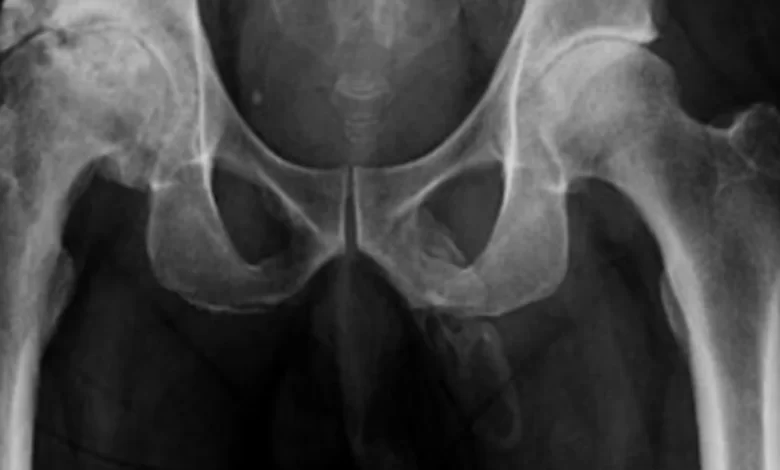

Al practicar un examen de rayos X en la zona de la cadera, los médicos advirtieron algo inusual. Las imágenes mostraban una extensa calcificación de los tejidos blandos que forman el pene.

Tras varias semanas de investigación, los médicos descubrieron que el paciente sufría osificación del pene, una condición sobre la que apenas existen 40 casos registrados. La condición ocurre cuando se depositan sales de calcio en los tejidos blandos del órgano, provocando la aparición de placas de hueso donde no debería de haberlas.

Según los médicos que firman el informe de Urology Case Reports, el paciente de 63 años tenía esa misma enfermedad, pero los médicos no pudieron realizar pruebas adicionales para confirmarlo porque el hombre se negó a someterse a más pruebas o a tratamiento pese a que la calcificación se había extendido por toda la longitud de su miembro.